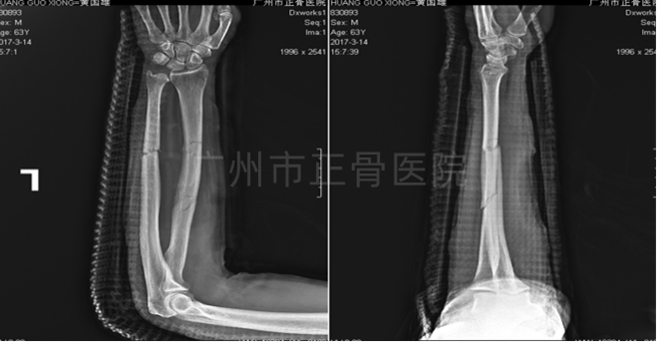

X线片检查结果:左侧桡尺骨双骨折,其中桡骨为多段骨折,位线尚可;尺骨骨折远端向下移位,向桡侧成角。

▲复位前,骨折明显成角移位

▲复位后,骨折对位对线良好